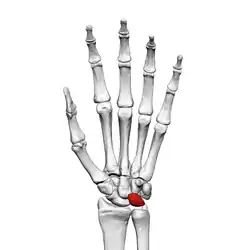

![]() Left hand anterior view (palmar view). Lunate bone shown in red. | |

The lunate bone (semilunar bone) is a carpal bone in the human hand. It is distinguished by its deep concavity and crescentic outline. It is situated in the center of the proximal row carpal bones, which lie between the ulna and radius and the hand. The lunate carpal bone is situated between the lateral scaphoid bone and medial triquetral bone.